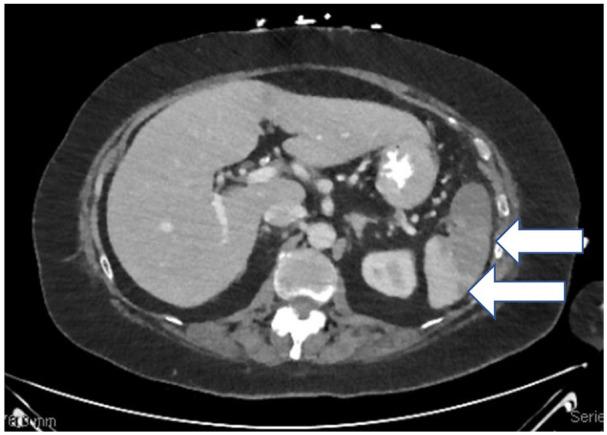

Splenic infarction is an uncommon cause of abdominal pain. In this article, we present a case of isolated splenic infarction presenting with severe abdominal pain, nausea, and with associated generalized weakness. Computed tomography (CT) abdomen and pelvis with contrast revealed multiple splenic infarctions of the entire lower pole with occlusion of the branch splenic arteries, while CT abdomen without contrast was unremarkable. Etiology was later revealed to be thromboembolism secondary to atrial fibrillation. It was managed with anticoagulation. To our knowledge, this is the second case of splenic infarction presenting as an initial manifestation of atrial fibrillation (AF), reported in the literature.

脾梗死是腹痛的一种不常见原因。本文报告了一例以严重腹痛、恶心和全身无力为表现的孤立性脾梗死。腹部和骨盆 CT 增强扫描显示整个下极有多处脾梗死,脾动脉分支闭塞,而腹部 CT 平扫未见异常。病因后来被确定为房颤继发的血栓栓塞。给予抗凝治疗。据我们所知,这是文献中报道的第二个以房颤(AF)首发表现的脾梗死病例。